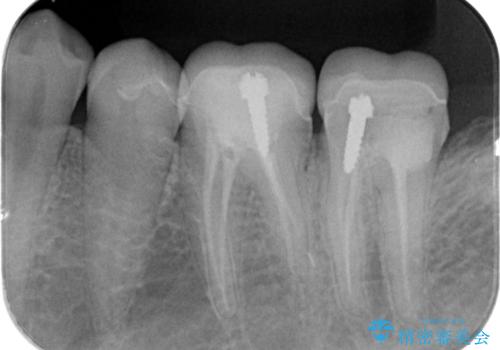

割れたクラウン 再発した虫歯の治療

- 「他院で治療したクラウンが破損したまま放置してしまった、治療したい。」、とセラミック治療を希望され来院されました。

欠けたクラウンの下には虫歯が再発し、このまま放置すると抜歯を余儀なくされる状態です。

虫歯をマイクロスコープを用いて丁寧に除去した後、ジルコニアセラミッククラウンによるクラウン製作を行います。